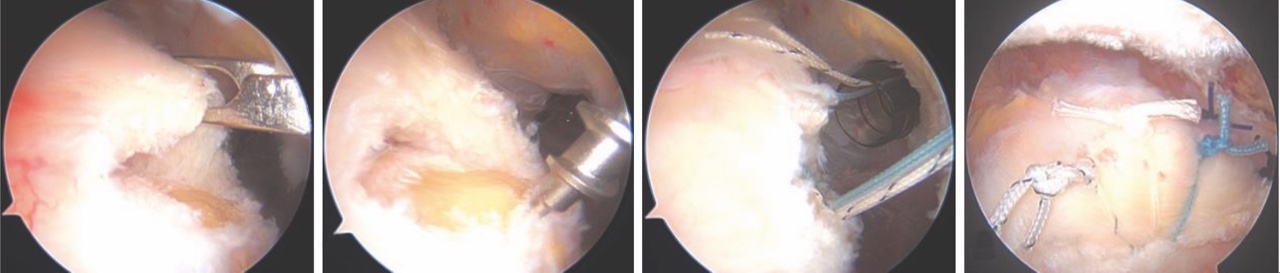

Nella tecnica artroscopica, sono disponibili diverse configurazioni di riparazione con utilizzo di ancore: Single-Row (SR – singola fila di ancore laterale) (Fig. 2), Double-Row (DR – doppia fila di ancore, una mediale e una laterale) e Suture Bridge (SB – doppia fila di ancore con suture incrociate che mimano una riparazione transossea).